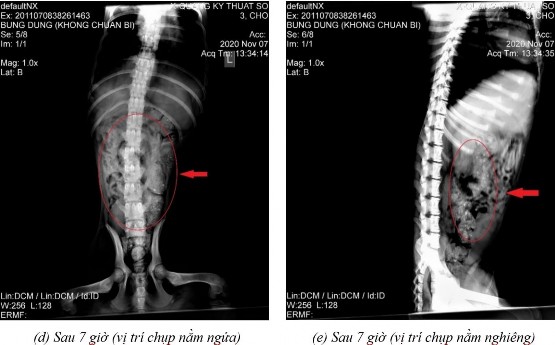

Phụ lục 5.4. Hình ảnh X-quang chó 5 ở thời điểm (a) sau 2 giờ 20 ở vị trí nằm nghiêng, (b) sau 4 giờ ở vị trí nằm ngửa, (c) sau 4 giờ ở vị trí nằm nghiêng, (d) sau 7 giờ ở vị trí nằm ngửa, (e) sau 7 giờ ở vị trí nằm nghiêng, (f) sau 9 giờ ở vị trí nằm ngửa, (g) sau 9 giờ ở vị trí nằm nghiêng, (h) sau 11 giờ 40 ở vị trí nằm ngửa và (i) sau 11 giờ 40 ở vị trí nằm nghiêng